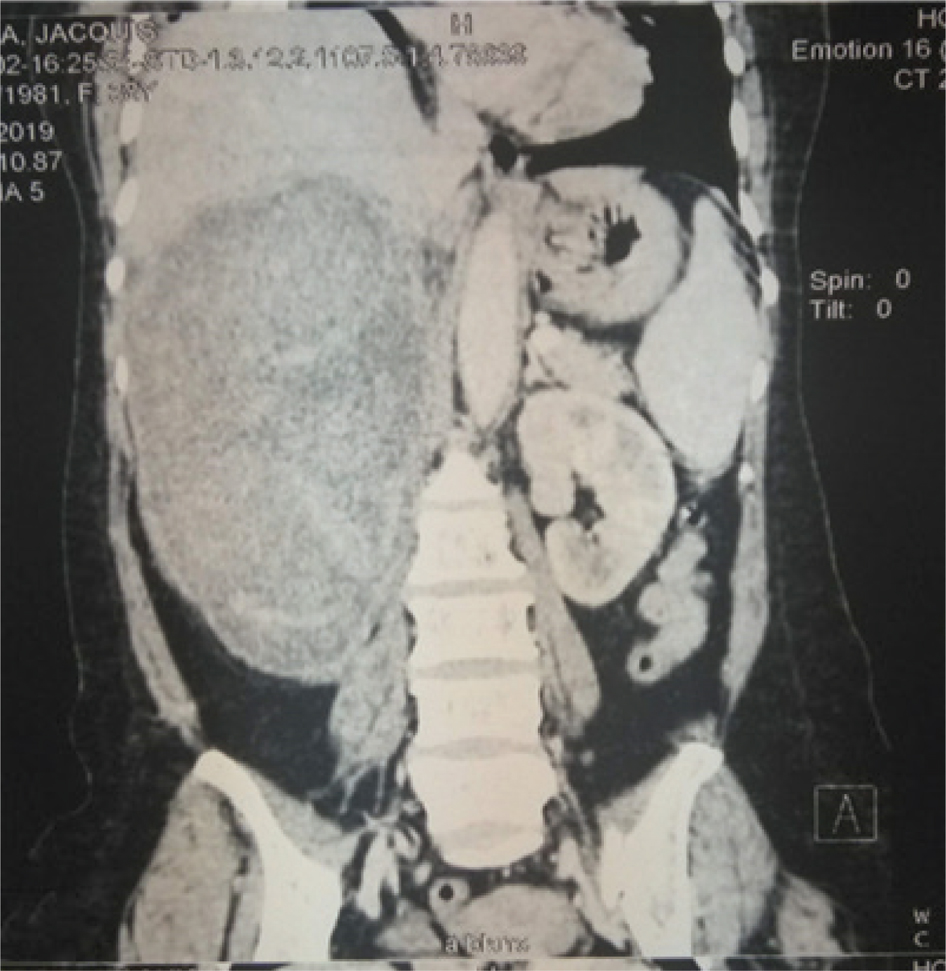

Fig 2

Figure 2: A contrast CT-scan showing a cystic right renal tumor in the upper pole with associated hydronephrosis. Courtesy: Grand Yoff Hospital.

CT-scan or MRI findings of cystic renal lesion, Bosniak class I and class II, have minimum risk of malignancy and require no follow-up. However, Bosniak class IIF has a 10% risk of malignancy and follow-up with ultrasound or CT is recommended. Bosniak class III and IV have 65% and 92% risk of malignancy respectively and require treatment (Figure 2) (9).